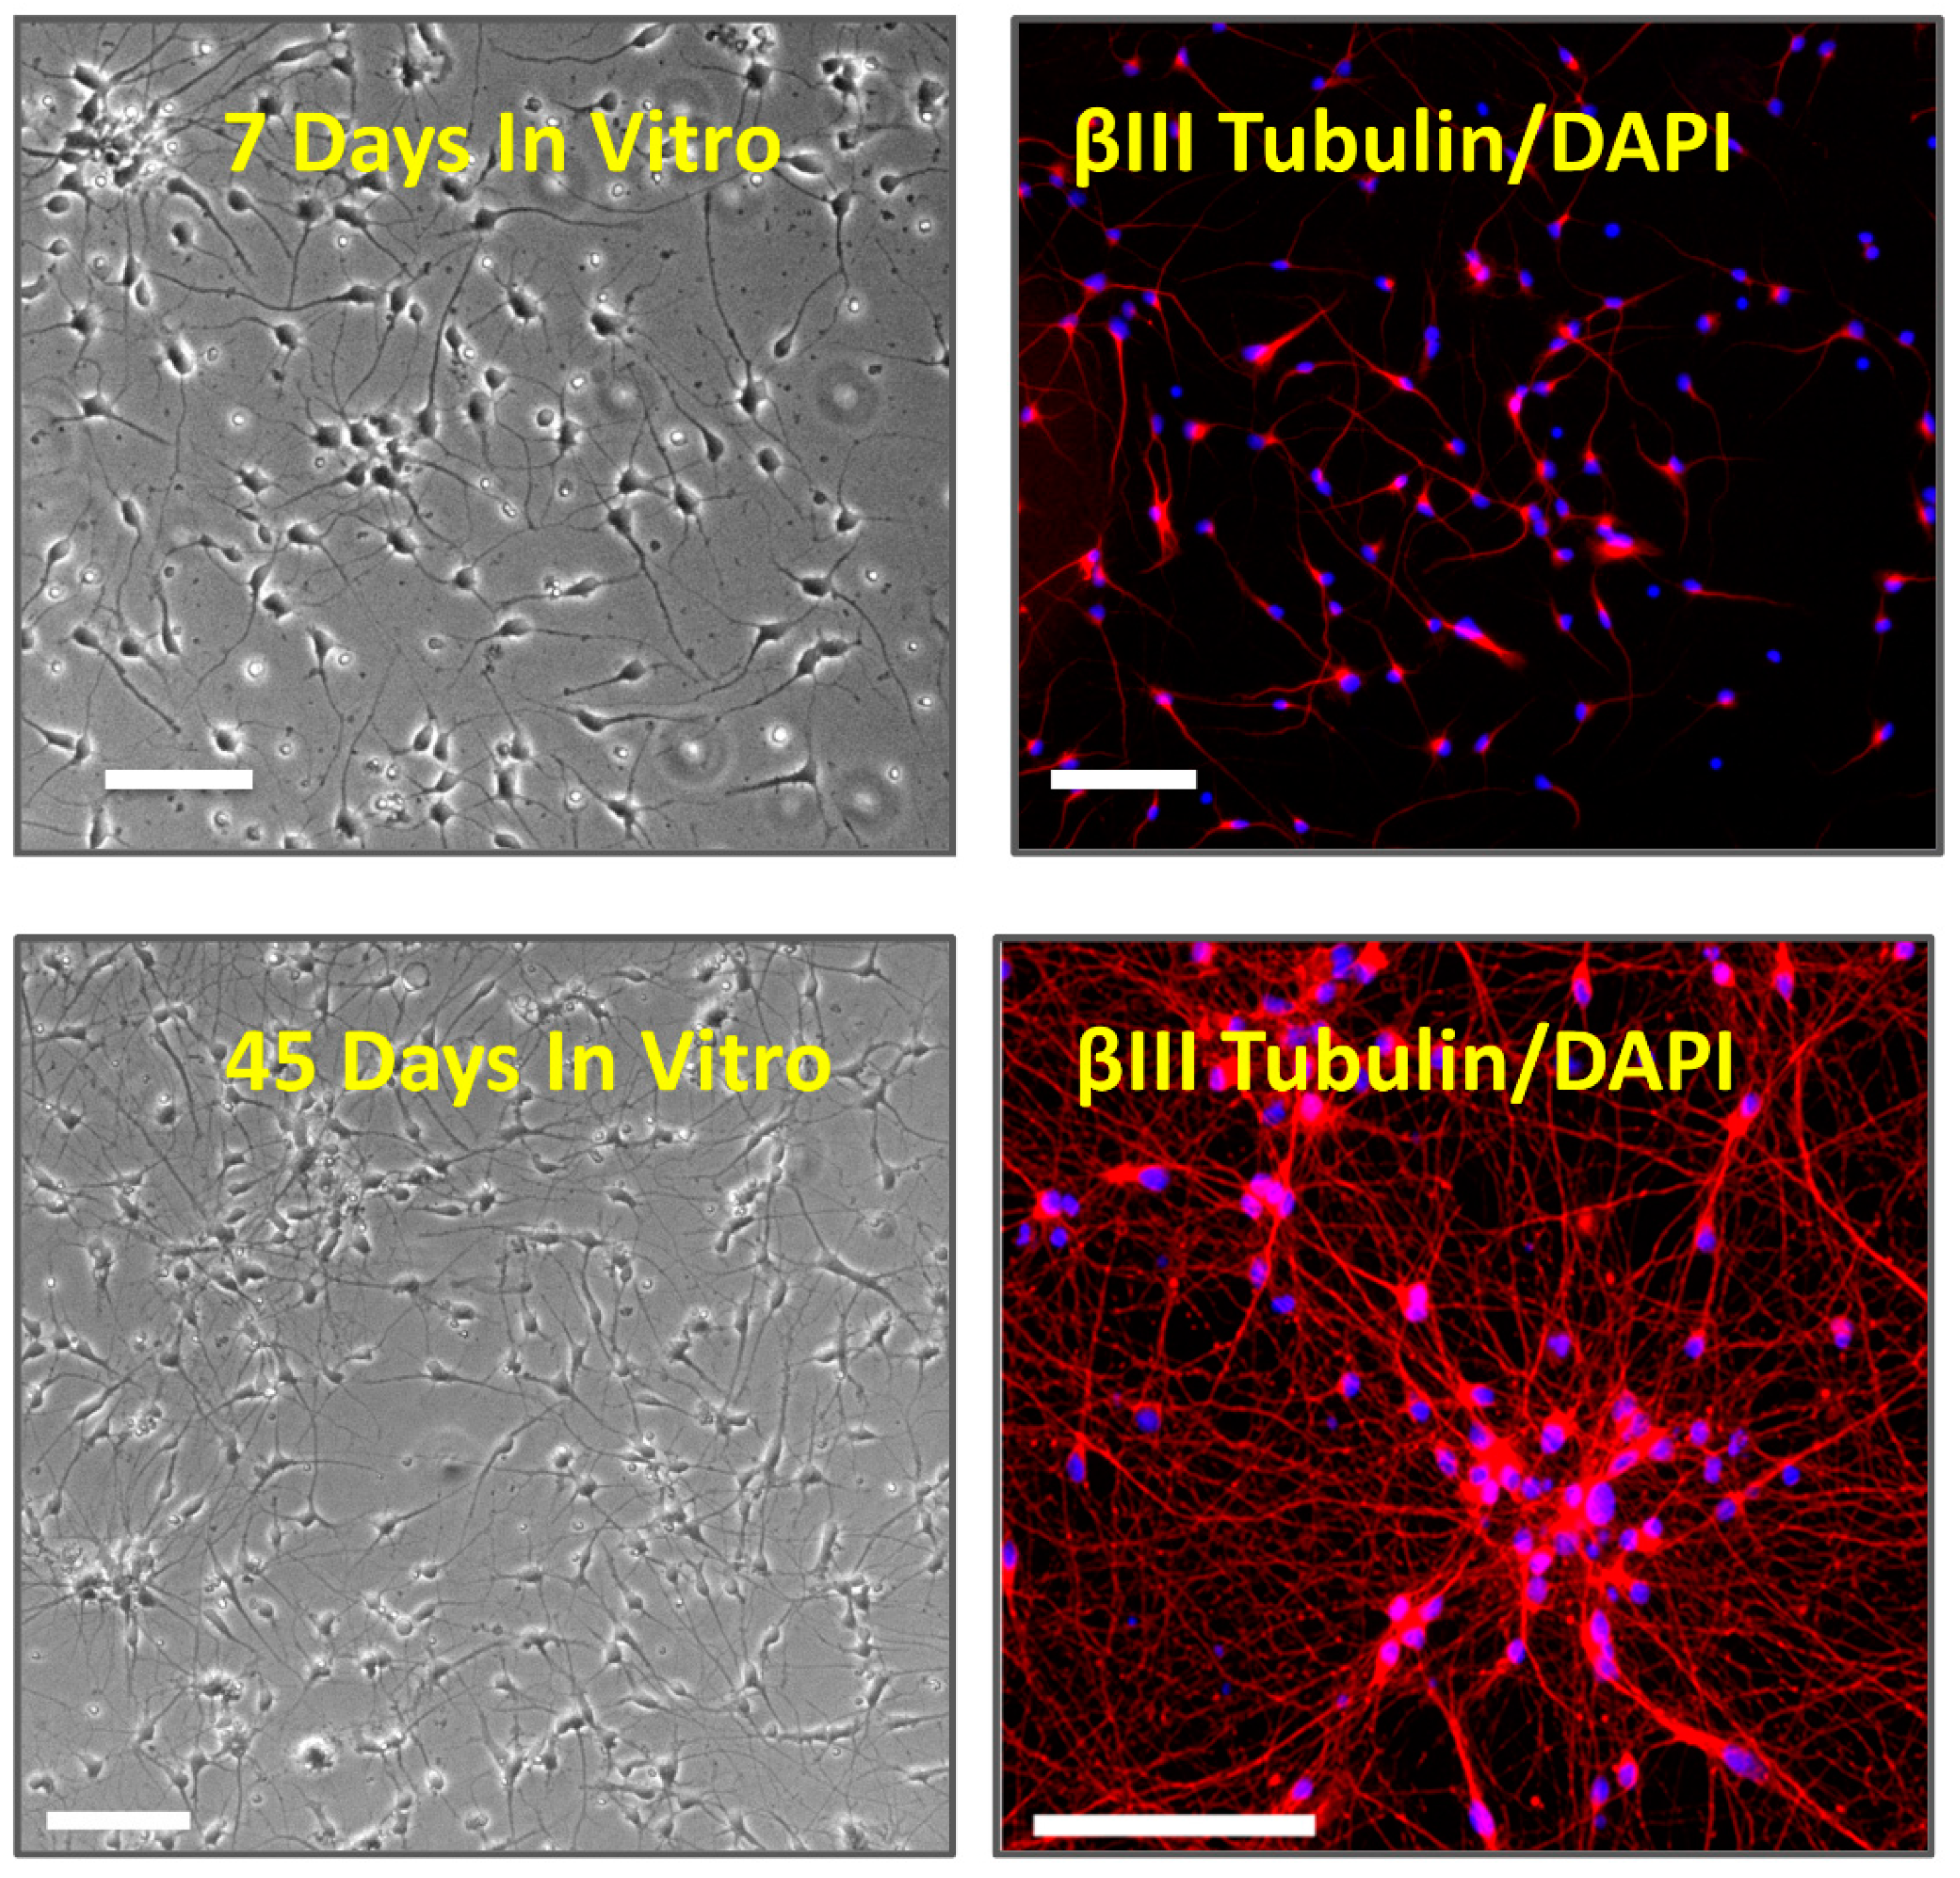

2.1. Cell Culture

2.2. Immunocytochemistry

3.1. Multi Electrode Array